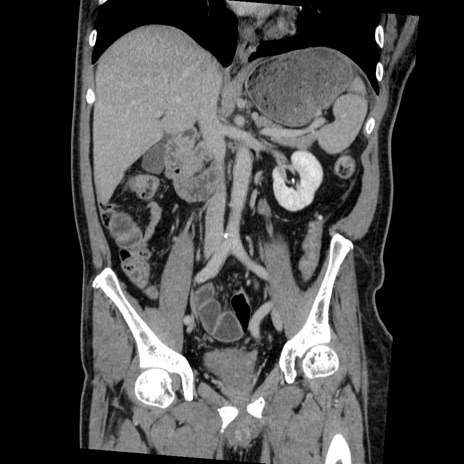

症例22(冠状断像)

【症例】50歳代男性

【主訴】腹痛

【現病歴】AVMからの被殻出血のため回復期リハ病棟入院中。 本日午後3時頃急に下腹部痛が出現した。

【既往歴】AVM、被殻出血、虫垂炎、高血圧

【身体所見】意識晴明、左半身不全麻痺、会話の理解は良好、36.5°C、腹部:膨隆、全体に板状硬、下腹部正中に圧痛点あり、反跳痛-、筋性防御不明、右下腹部にope scar

【データ】WBC 9400、CRP 0.06